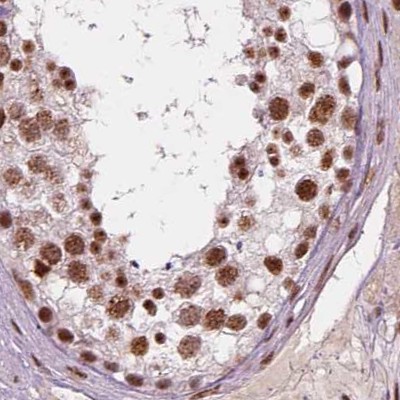

Immunohistochemical staining of human cerebral cortex, gastrointestinal, placenta and testis using Anti-ELF2 antibody HPA071166 (A) shows similar protein distribution across tissues to independent antibody HPA006057 (B).